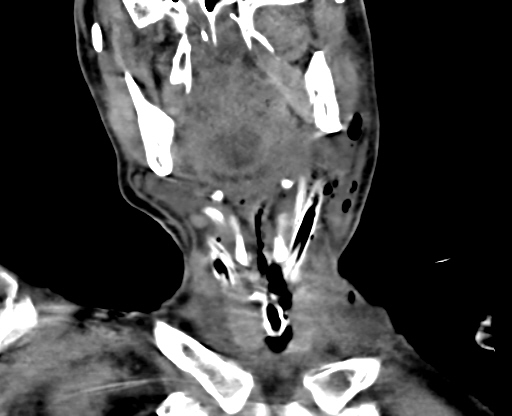

经过十七天的治疗,医护人员与死神来回拉锯,患者的颌面部、颈部红肿、疼痛以及肺部感染等症状明显缓解,体温恢复正常,逐渐脱离呼吸机。目前,患者已转入普通病房,拔除全身引流管,可下床活动,全身状况好转。

▲治疗第5天颈部(冠状位),胸部(轴位)